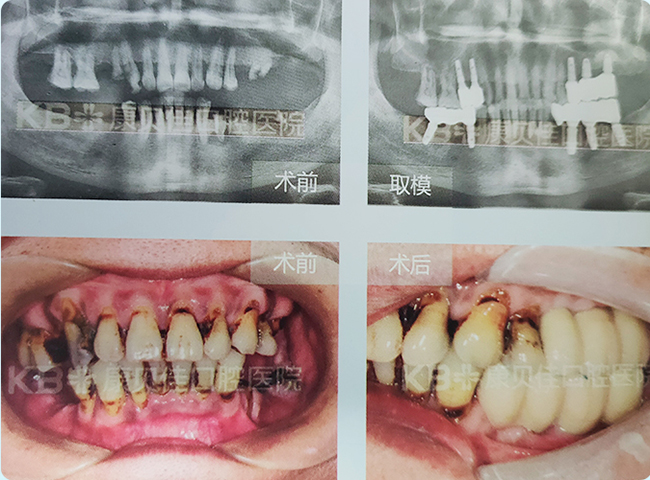

买先生 52岁

牙齿缺失后吃饭不香,非常苦恼。尝试过活动假牙,但感觉不舒服,对比之后决定种牙。但因为牙槽骨条件太糟糕,很多医疗机构不愿意给其种牙,在朋友介绍下来到康贝佳。设计的方案为上颌窦外提升的同时植入种植体,戴牙后感觉像真牙一样好用!

治疗方案:

上颌 种植5颗 下颌 种植5颗恢复7颗